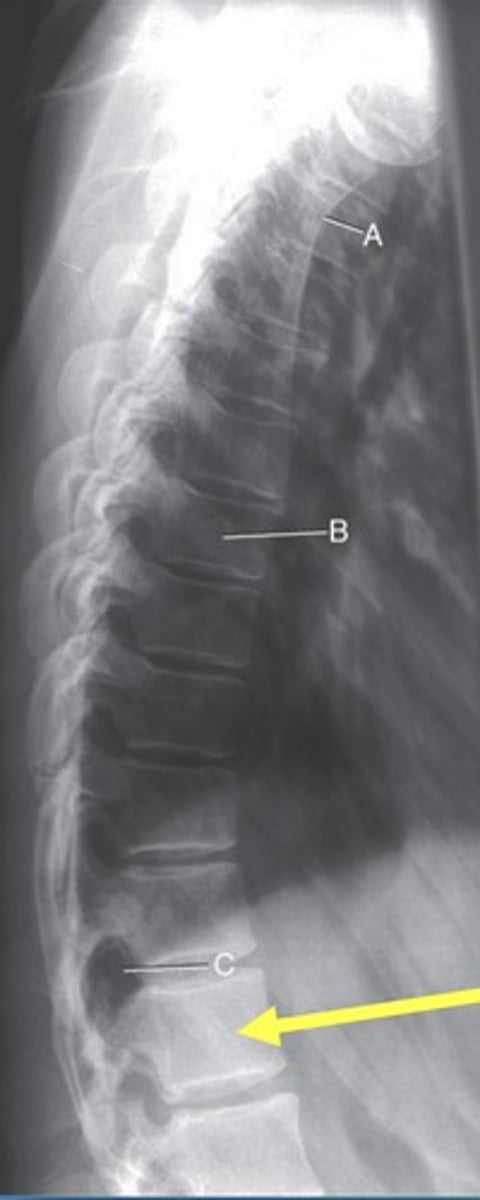

T3 body

A.

T7 body

B.

T11-12 intervertebral foramen

C.

Lateral T-spine

What position?